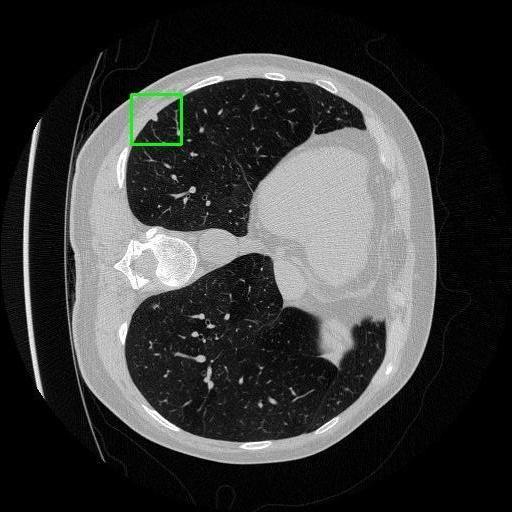

We developed an AI-based system using deep learning models for analyzing lung CT scans to detect and classify pulmonary nodules. We chose the YOLOv11 architecture for its enhanced object detection capability and adapted it specifically for medical imaging, incorporating pixel-level precision and severity classification.

Classification into three severity levels with colored bounding boxes.

Successfully built and deployed an AI model (YOLOv11) capable of detecting lung nodules in CT scans with high accuracy and real-time performance.

Designed a severity classification system that categorizes nodules into null, moderate, and severe using colored bounding boxes, assisting in rapid clinical decision-making.